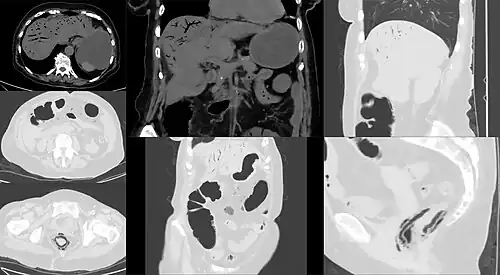

Computed tomography (CT) showing dilated loops of small bowel with thickened walls (black arrow), findings characteristic of ischemic bowel due to thrombosis of the superior mesenteric vein.

Computed tomography

Computed tomography (CT scan) is often used.[29][30] The accuracy of the CT scan depends on whether a small bowel obstruction (SBO) is present.[31]

Early findings on CT scan include:

• Intestinal mesenteric edema[29]

• Bowel dilatation[29]

• Bowel wall thickening[29]

• Intestinal mesenteric stranding[32]